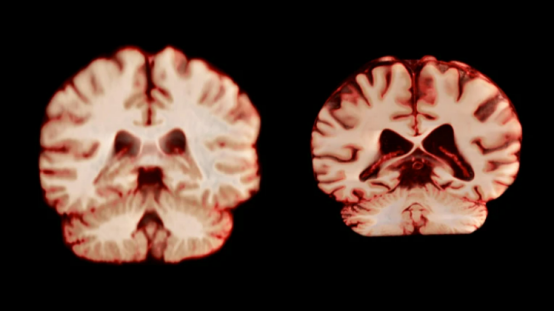

健康的大脑(左)和受阿尔茨海默病影响的大脑。图源:Nature,Anatomical Travelogue/SPL

据《自然》新闻报道,挪威奥斯陆大学的研究团队最近发表在《美国国家科学院院刊》上的一项重磅研究,用超大规模的纵向脑成像数据给出了明确答案:健康大脑衰老的性别差异,不太可能解释女性更高的AD患病率。这一发现,彻底颠覆了我们对AD性别差异的传统猜想。